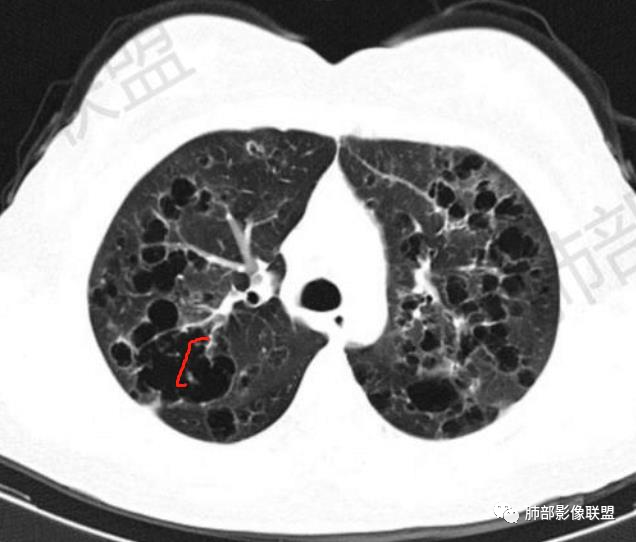

双肺多发不规则囊腔,囊壁增厚,并可见散在分布的结节与实变,多层面观察较多囊腔沿支气管走行分布,年轻女性双肺多发囊,但囊腔不规则,一般不考虑Lam,有结节及囊,有实变〈粘液拴〉年轻女性,首选PLcm或ccam

晨读:女,31,间断咳嗽、咳痰9月。卵巢交界性囊腺瘤术后。胸部CT:双肺多发大小不等薄壁囊腔影,部分融合,形态不规则,个别囊壁偏厚。右肺上叶及左肺下叶纤维索条影。左下叶不规则囊腔影,壁不均匀增厚,周围不规则实性成分加GGO,放射性毛刺,胸膜牵拉。考虑:囊腔型Ca?转移?鉴别PLCH,Lam,LIp,BHD,CF,CPAM等,听大咖解析。

胸部CT:两肺多发囊腔,中上肺受累为主,囊腔形态不规则(囊有点丑),分叶状,囊壁厚薄不均,大部分囊壁薄。尚有一些结节影。

晨读病例囊长得不漂亮,也没有呼吸困难等症状,不怎么支持LAM。

4.PLCH:常见于吸烟青年男性,囊腔形态不规则,呈分支状,囊壁厚薄不均,双侧肋膈角常不受累。

晨读囊不规则,分叶,存在PLCH可能,但为不吸烟女性,可能性下降。

晨读病例有妇科肿瘤手术史,肺内病变转移瘤可能性大(而且一般盆腔肿瘤手术前基本都会完善胸部X检查,能够顺利完成手术估计手术时肺内无明显病灶),但肺囊肿有较明显的融合,这在转移瘤中较少见。综合上述考虑囊腔型肺转移瘤,鉴别PLCH。